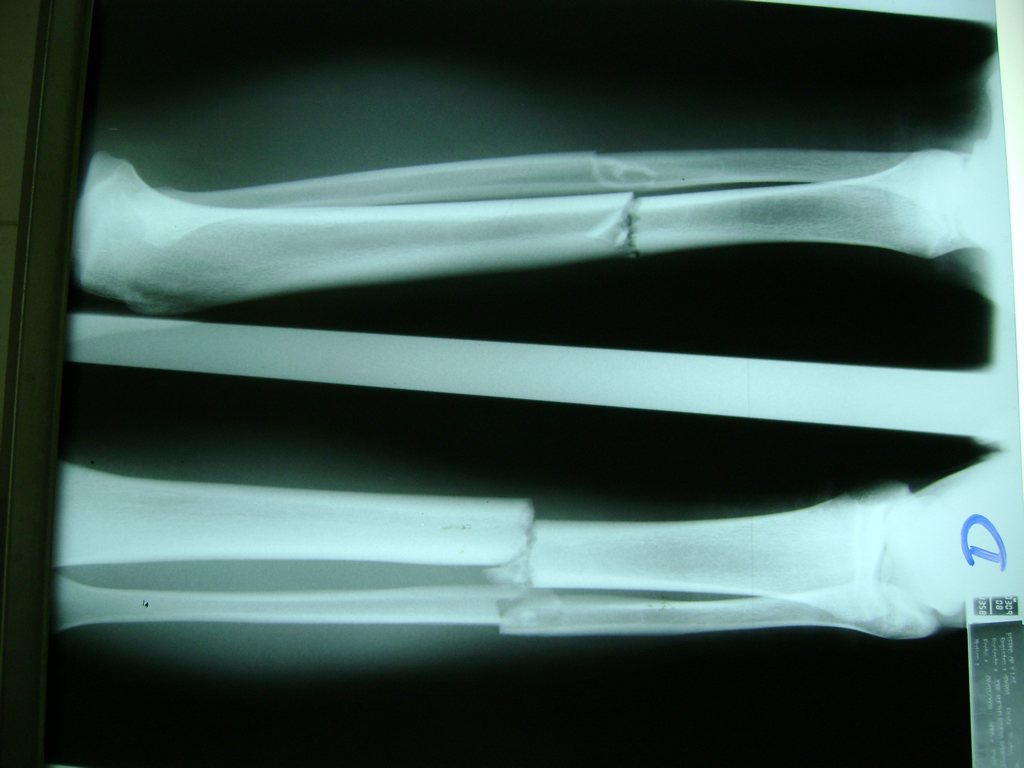

Húmero - Perone y Tibia

Aunque cada uno de estos huesos puede fracturarse por separado, normalmente la rotura es una lesión que se produce de forma conjunta

La mayor parte de las roturas implican a la parte proximal del hueso (parte del hueso próximo a la rodilla) o a la parte distal (parte del hueso cerca del tobillo).

Debido a la fina cobertura de piel que recubre la tibia y el peroné, las fracturas generalmente son abiertas, es decir, el hueso roto rasga la piel, atravesándola. Las fracturas de tibia y peroné generalmente se producen por un fuerte impacto o torsión.